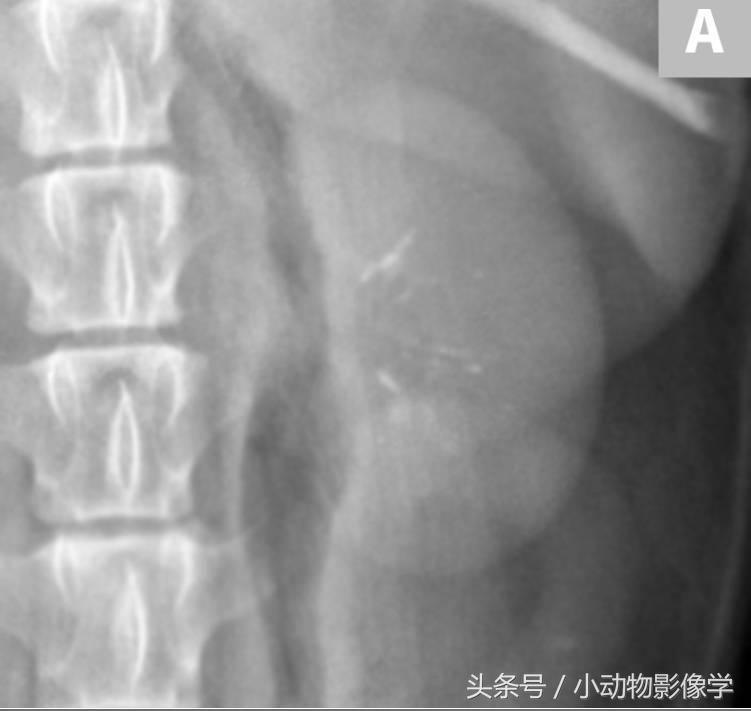

图3A、一只临床表现正常的犬X光片,这是左肾图像的特写图片,可见一个大块、边缘光滑的肾结石。

图3B、图3A中左肾的超声图像。可见结石的高回声平滑表面,和由矿化结石引起的明显的远端声影伪像(S)。